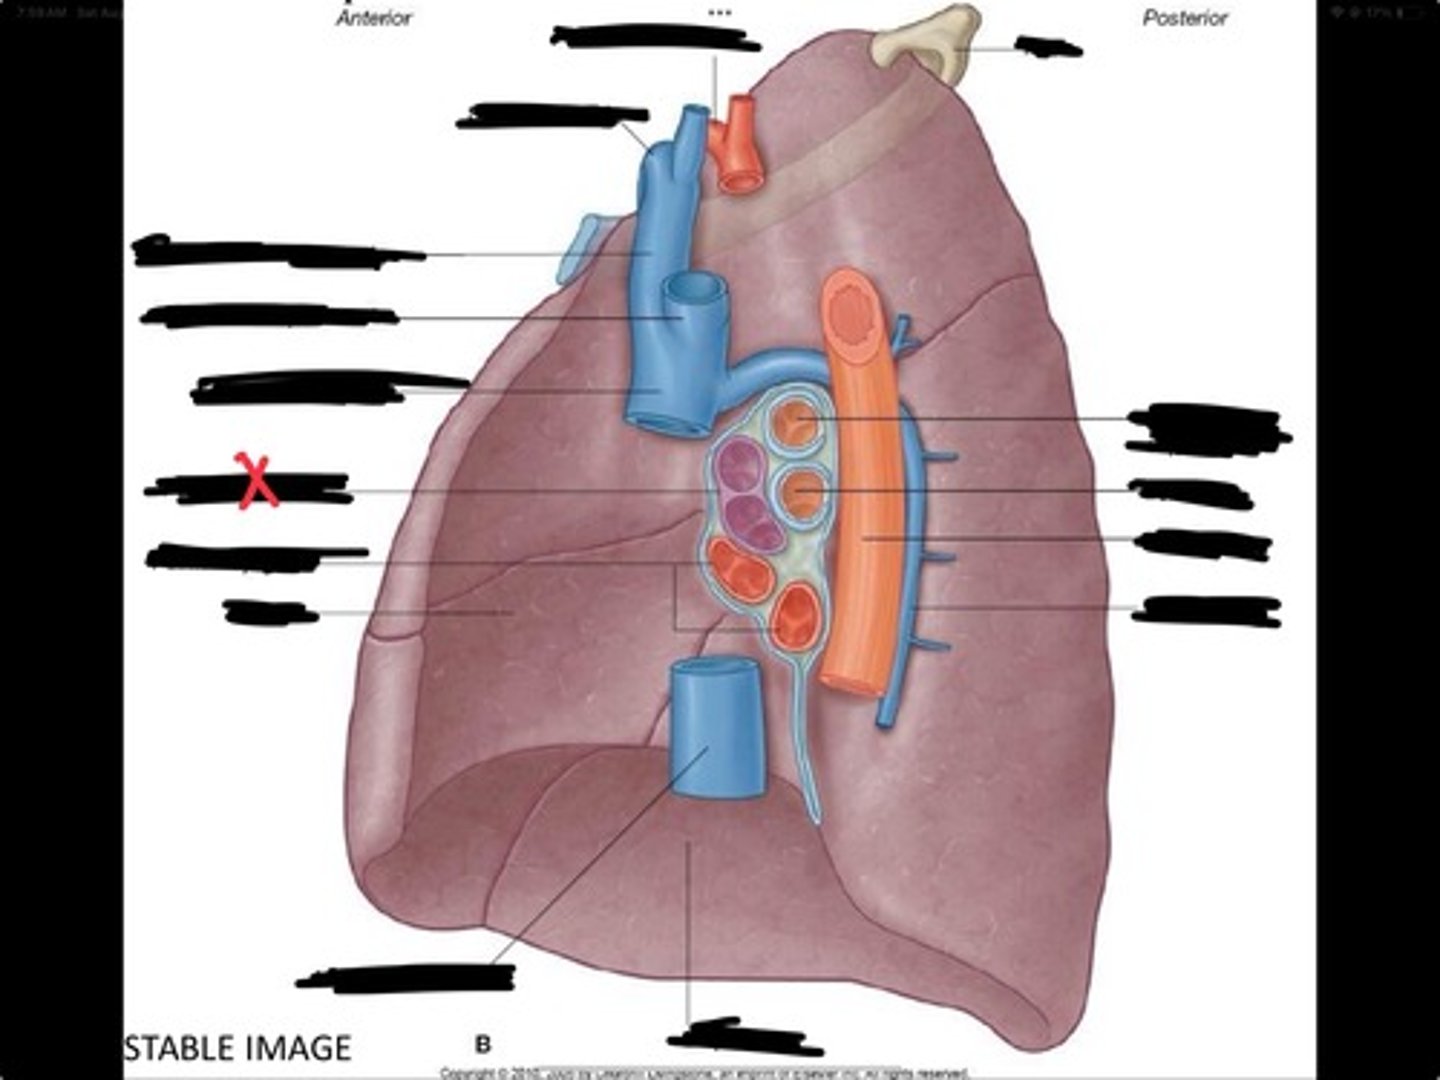

Lung

Pleural cavity

Visceral pleura

Parietal cavity

Esophagus

Bronchus

Pulmonary artery

Pulmonary vein

Pulmonary artery

Bronchus to superior lobe

Pulmonary veins